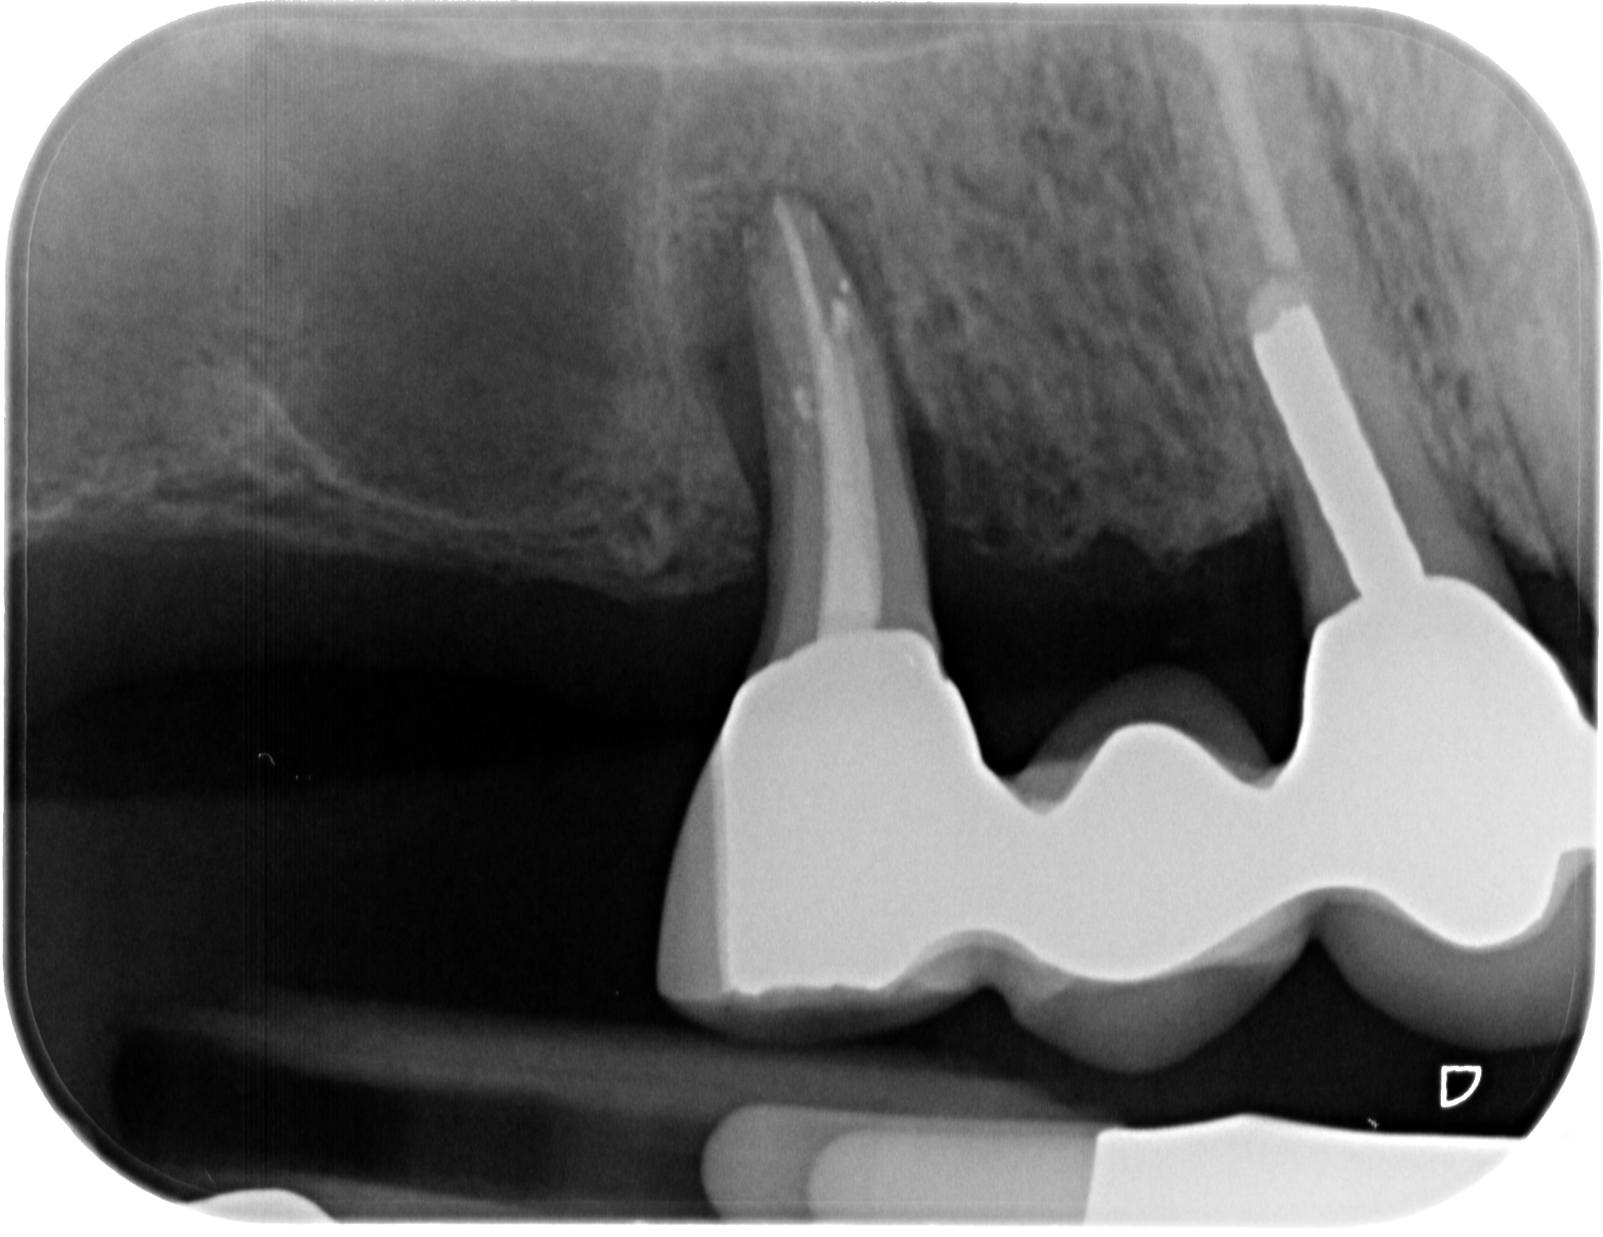

WF – Rö orthoradial mit Seitenkanal Veröffentlicht 24. Juni 2013 am 1603 × 1237 in Endo- Paro – Läsion